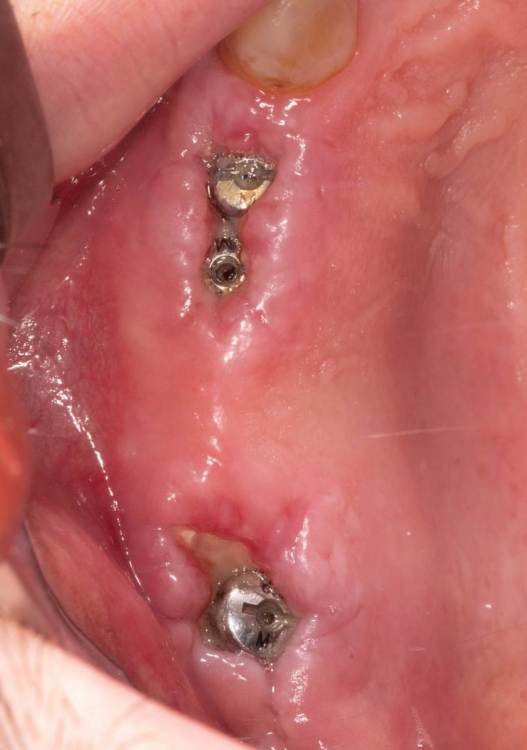

Женька Опубликовано 17 октября, 2021 Поделиться Опубликовано 17 октября, 2021 Перелом под десну, рядом мост 2.5-2.7, который конечно же пациент менять не хочет. Смущает дефект между клыком и 2.4, переходящий на вестибулярную пластинка 2.4. Как решали бы? Возможно только мягкими тканями закрыть? Пошли бы одномоментно или законсервировали бы? Ну и ангуляция имплантата, приемлемое ли положение для ортопедии выходит? Ссылка на комментарий

annda Опубликовано 17 октября, 2021 Поделиться Опубликовано 17 октября, 2021 У 5го что за костный карман такой? Ссылка на комментарий

Женька Опубликовано 17 октября, 2021 Автор Поделиться Опубликовано 17 октября, 2021 @annda думается мне последствия функциональной перегрузки. Ну и это штамповки, которым лет 5 уже. Может в них причина? Ссылка на комментарий

Женька Опубликовано 11 января, 2022 Автор Поделиться Опубликовано 11 января, 2022 Как я и говорил? купил объектив, теперь буду больше своих косяков фотографировать и выкладывать. Наконец-то руки дошли и машина доехала обратно до Башкирии и прооперировал пациента. Аккуратно сняли мост путём отпиливания по коронкам, удалили зубы достаточно быстро. Долго ловил пилотной фрезой дентиум правильное положение... так и не поймал. Вспомнил как Пётр Лазукин использует фрезу на турбинке для пилотного сверления и о чудо, сразу появилось устойчивое направление и линдеман перестал соскакивать, спасибо за видосики Петру Ну и далее по протоколу, пилотное положение 2.4 и 2.5 менял по 3 раза каждый (а в итоге всё равно не доволен получившимся направлением и судя по всему слишком близко) 2.7 с синуслифтингом. В лунки A-oss, сверху мембрана от Владмивы. И заживление через 9 дней. К сожалению, фото швов и той порнографии, что была сделана с лунками и мембраной нет. Резюмируя, это были 35-38 имплантаты которые я поставил, я уже чувствую себя намного увереннее (когда как Пётр турбиной пилотную точку сделал вообще в себя поверил ), но проблемы с позиционированием ещё долго будут меня преследовать. Жду критику и помидоры за РГ контроль. Ссылка на комментарий